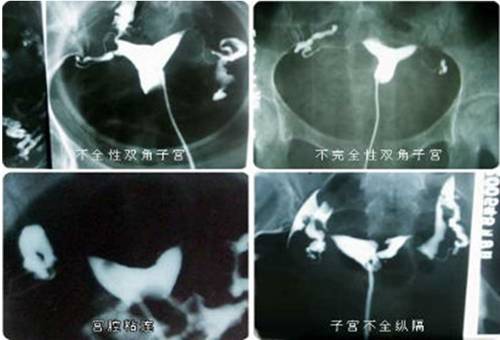

输卵管造影技术是不孕症患者的检查方法,它能清楚地显示子宫腔形态、大小,内壁情况,输卵管走行、通畅与否,狭窄部位、伞部情况及盆腔环境,并有一定治疗作用。一次确诊率高于90%,输卵管阻塞单经此造影后3个月内怀孕者占27%,无痛苦、动态显影、清晰可视!

输卵管造影技术通过导管将造影剂持续贯注入宫腔,医生可持续观看宫腔和输卵管动态影像,不但能知道子宫腔形态、输卵管是否通畅及阻塞的部位和程度,还能对轻度输卵管阻塞有疏通功效,所以它是不育症的必检项目。

(1)不孕症:用以了解原发性或继发性不孕症的原因,它不仅能了解子宫及输卵管有无先天性畸形或病理情况存在,还能了解输卵管是否通畅,从而找到不孕原因。

(4)畸形诊断:子宫畸形如双角子宫、纵隔子宫等。

(6)粘连诊断:宫腔粘连、宫颈粘连等。